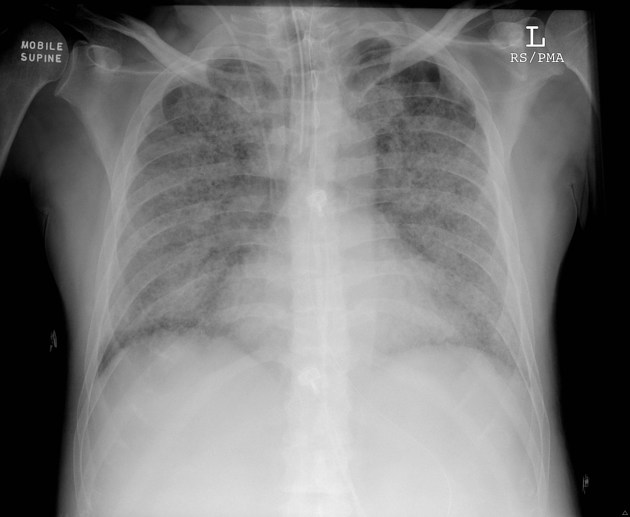

폐렴(pneumonia)은 폐의 세기관지와 폐포에 염증이 발생하는 감염성 질환으로, 박테리아, 바이러스, 곰팡이 등 다양한 원인에 의해 발생한다. 경증에서 중증까지 다양한 임상 양상을 보이며, 면역력이 저하된 환자나 기저질환이 있는 경우 치명적일 수 있다.

중증 폐렴에서는 폐포 내 삼출물(흔히 진물이라고 말하는 것과 비슷한 것)의 증가로 인해 산소와 이산화탄소 등 가스 교환이 어려워지면서 저산소증(hypoxemia)이 발생한다.

특히 급성호흡곤란증후군(Acute respiratory distress syndrome, ARDS)이 동반되면 산소 공급이 어려워지고 기계 환기(ventilator)에도 반응하지 않는 경우가 많아 환자의 예후, 즉 치료 결과가 나쁠 가능성이 높다.